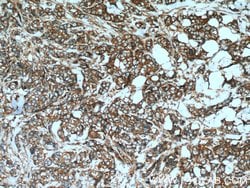

| Western Blot, Immunohistochemistry (Paraffin) | |